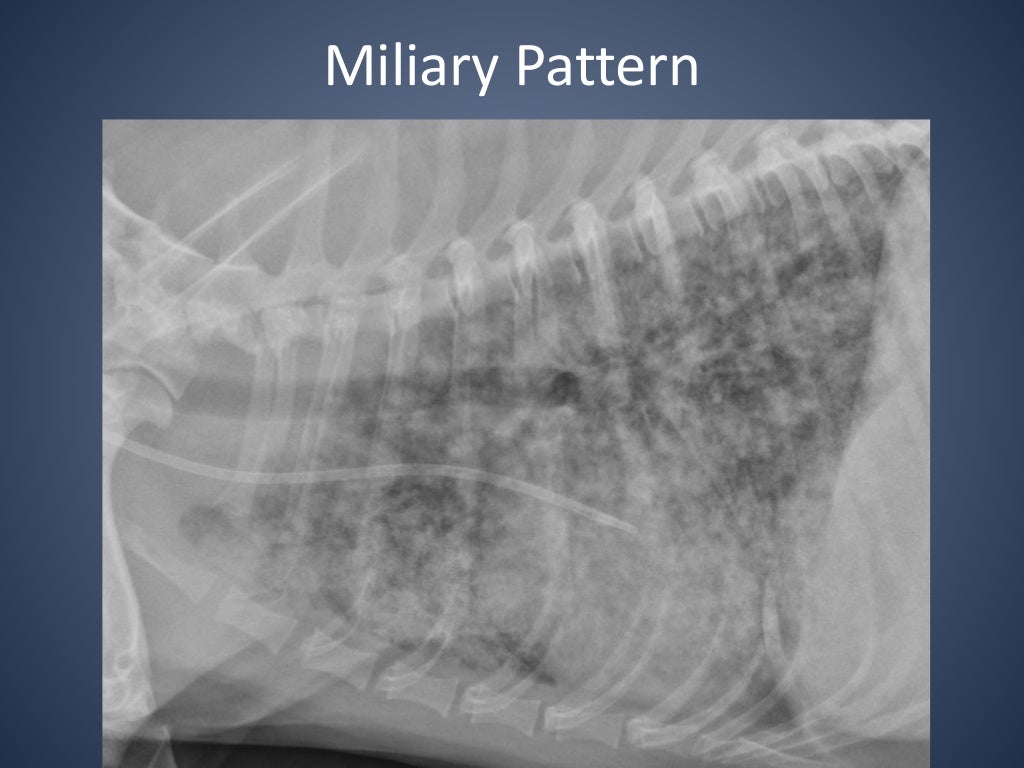

From www.slideshare.net

The Radiographic Approach to the Coughing Dog Kennel Cough Xray The prominent clinical sign of kennel cough is a cough that sounds like a goose honk that may be followed by retching and gagging. Thoracic radiographs are recommended for any patient with: Find specific details on this topic and related topics. There’s a good chance they’re suffering from an upper respiratory infection. Signs of systemic illness (eg, lethargy, decreased appetite).. Kennel Cough Xray.